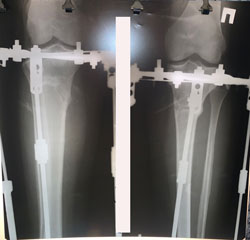

рентген перед снятием аппаратов

Вложения

image-30-11-20-10-25-5.jpg

image-30-11-20-10-25-4.jpg

Срок сращения 89 дней.